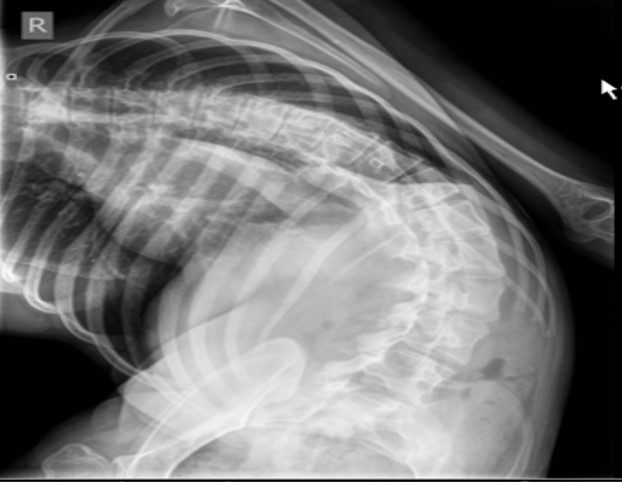

Особенности ведения периоперационного периода пациентов с декомпенсированным сколиозом глазами врача анестезиолога.

Физическое состояние пациента